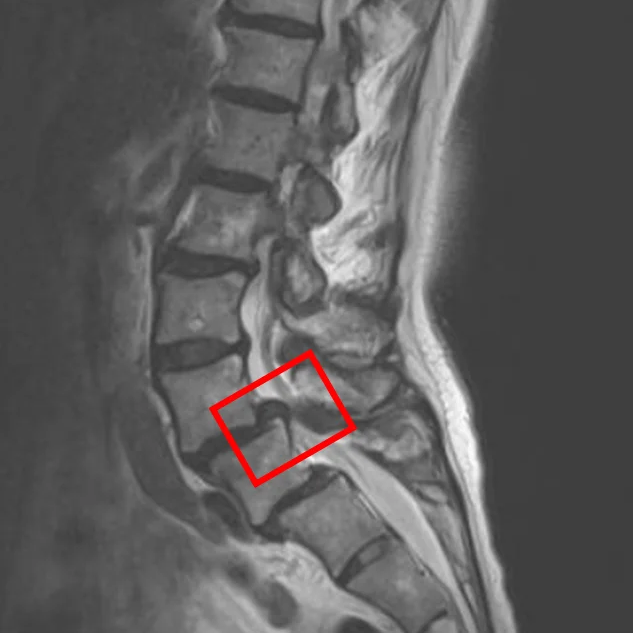

По данным МРТ и результатам осмотра пациентки выявлен стеноз позвоночного канала L4/L5, спондилолистез позвонков L4 и L5.